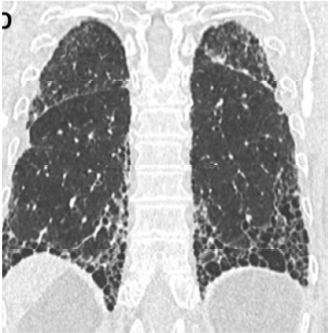

Paciente com 75 anos de idade, masculino, procedente de Minas Gerais, é encaminhado da atenção básica, devido a um quadro de tosse crônica seca (início há alguns anos) associado a dispneia que vem piorando (atualmente mMRC 3).

No interrogatório sintomatológico, o paciente relata também apresentar sintomas de refluxo com certa frequência. Ele nega sintomas de vias aéreas superiores, chiado torácico, febre, perda ponderal e dores articulares.

Antecedentes pessoais: o paciente relata ter diabetes e hipertensão arterial sistêmica, com uso regular de metformina e valsartana, nega história de infecções respiratórias prévias recorrentes e doenças reumatológicas diagnosticadas. O paciente afirma que nunca fumou.

História ocupacional/exposições: o paciente relata que trabalhou a vida toda em escritório, um ambiente que ele diz ser arejado e sem poeira, e também nega ter contato com aves, mofo e travesseiro de pena.

No exame físico: verifica-se bom estado geral do paciente, anictérico, orientado em tempo e espaço, com frequência respiratória de 28 irpm, frequência cardíaca de 99 bpm, pressão arterial 130 × 80 mmHg e saturação de oxigênio em ar ambiente de 89%.

Aparelho respiratório: sons respiratórios presentes bilaterais, com crepitações teleinspiratórias em regiões infraescapulares e axilares posteriores, sem uso de musculatura acessória.

Aparelho cardiovascular: ritmo cardíaco regular, hiperfonese de componente P2 em foco pulmonar, sem sopros.

Extremidades: discreto edema de membros inferiores bilateral, sem sinais de trombose, tempo de enchimento regular de 2 segundos e presença de baqueteamento digital.

O paciente traz uma tomografia prévia solicitada pelo médico de família e representada nas imagens a seguir.

American Journal of Respiratory and Critical Care Medicine. Volume 198 Number 5 September 1 2018 (com adaptações).

Considerando a principal hipótese diagnóstica para o caso clínico hipotético apresentado anteriormente, julgue os itens a seguir.

I Geralmente a doença em questão ocorre em pacientes mais velhos, entre a sexta e a sétima década de vida. Frequentemente pacientes com esse diagnóstico apresentam como manifestação inicial uma exacerbação aguda.

II Os critérios diagnósticos são baseados na exclusão de outras causas de doença pulmonar, associados a padrão tomográfico específico ou combinações entre padrões tomográficos e histopatológicos.

III A broncoscopia pode auxiliar no diagnóstico. O esperado é que seja encontrada redução dos neutrófilos e(ou) linfocitose.

IV A reunião multidisciplinar (pneumologista, radiologista, cirurgião torácico e patologista), pode ajudar nos casos em que a tomografia sugere diagnóstico alternativo.

V Alguns diagnósticos diferenciais para o quadro descrito acima são: pneumonite de hipersensibilidade, doenças reumatológicas cursando com pneumopatia e toxicidade a drogas.

Estão certos apenas os itens